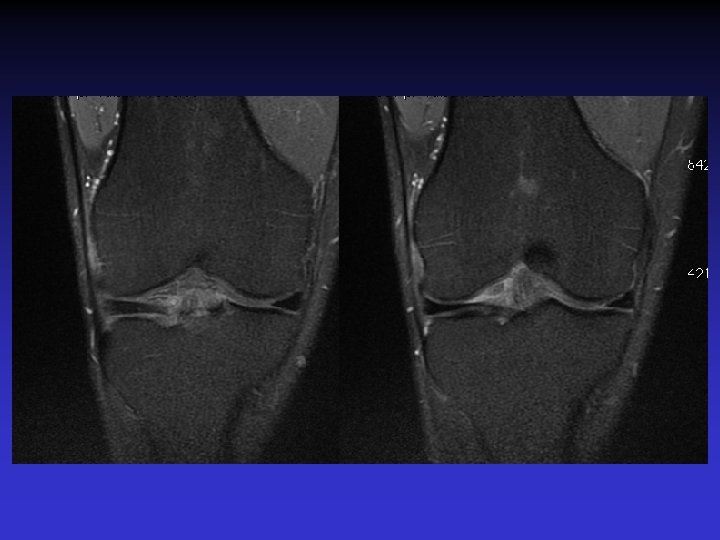

• • • Pas d’épanchement Pas de lésion méniscale Pas de lésion cartilagineuse Pas de lésion osseuse Anomalies du LCA • Épaissi • Hyper signal T 1 et T 2 • Orientation des fibres conservée • Kyste

ASPECT IRM • • Hyposignal TI Hypersignal T 2 Pas de prise du contraste après Gado IV Continuité conservée du LCA+++ avec dilacération des fibres • Aspect en « tige de céleri »

ATTEINTE BILATERALE • Non exceptionnelle • Concomitante ou décalée dans le temps

Mme S… 60 ANS DROIT

Mme S… 60 ANS GAUCHE